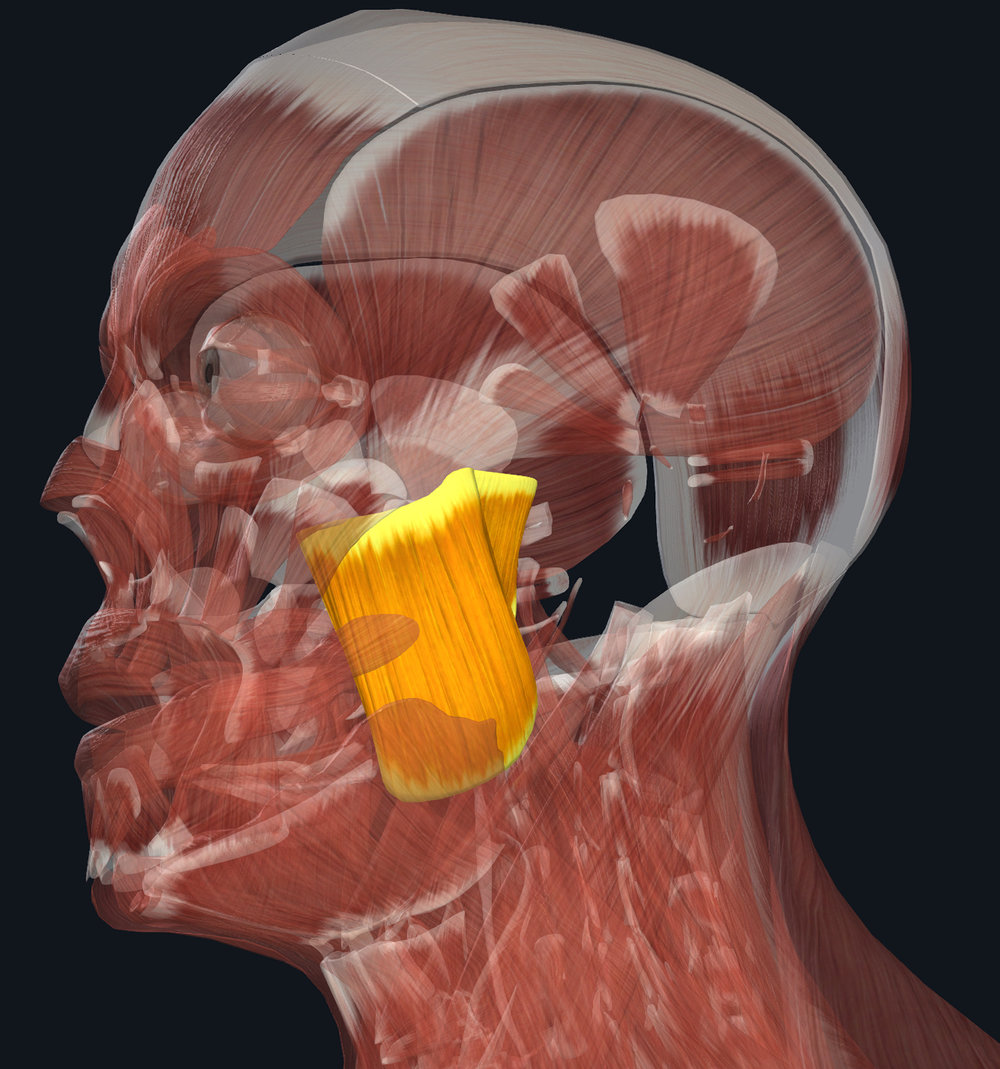

Dry Needling for TMJ Pain – PhysioFit of NC